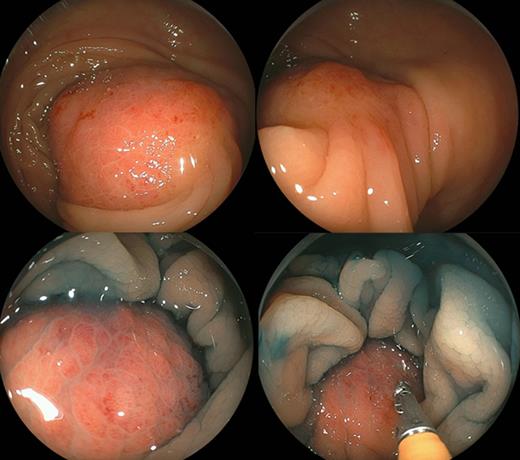

Colonoscopy revealed a 40-mm submucosal tumor with an inflamed surface in the transverse colon. The appearance of this lesion suggested a metastatic lesion from another site, and biopsy was performed, but did not provide a definitive diagnosis (Fig. 4). Laparoscopic right hemicolectomy was then performed. Histological examination of the resected specimen showed features of poorly differentiated SCC, similar to that previously seen in the cervical lymph nodes (Fig. 1b). There were no elevations of serum tumor markers. The patient was discharged 11 days after surgery without any complications. No further adjuvant treatment was given because of her poor general condition.

Colonoscopy reveals a 40-mm submucosal tumor with an inflamed surface in the transverse colon. Chromoendoscopy shows a tumor covered with normal mucosa. This lesion was a solid mass with a negative cushion sign (pressure applied to the tumor with a closed pair of biopsy forceps).